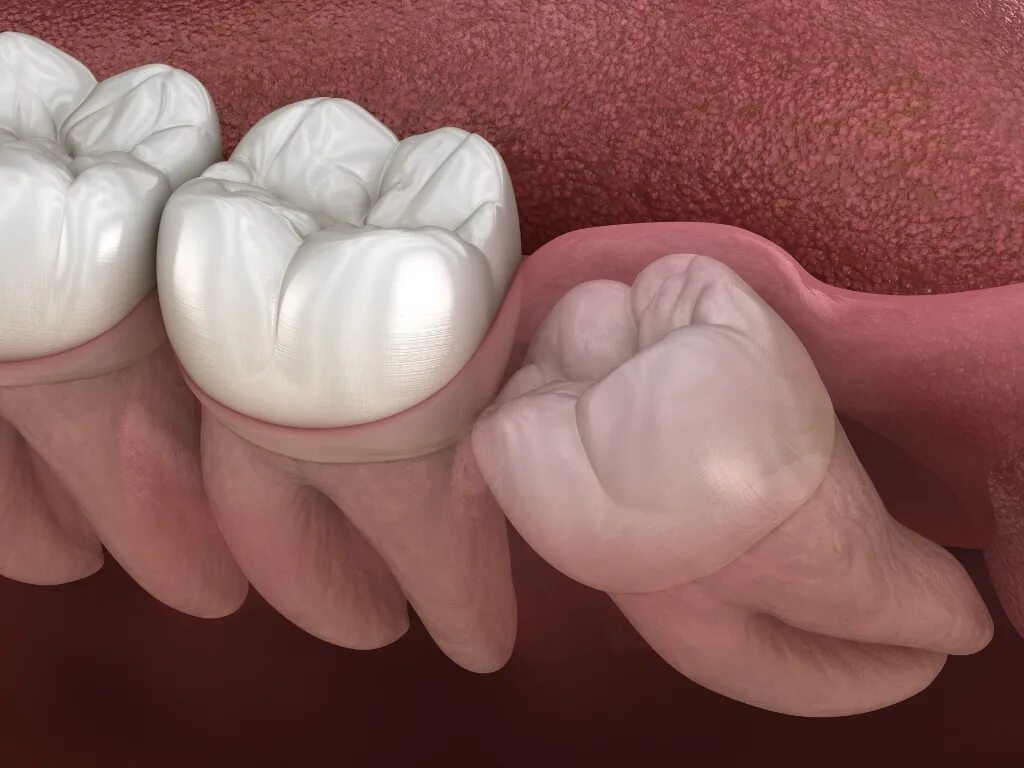

Удаленный зуб 8